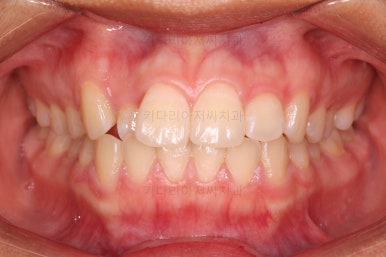

치열이 매우 바르게 되었고 교합도 양호하며 뻗쳐 있던 앞니 각도도 좋아졌네요.

돌출의 느낌도 처음보다 많이 좋아졌어요.

웃을 때 보이는 치열의 느낌도 좋고요.

전후 사진을 비교해 볼게요.

입술의 두께로 인한 돌출감 개선에 약간은 한계가 있었지만 그래도 본인이 만족한 수준에서는 돌출감을 개선했고 치열도 매우 가지런하게 마무리를 할 수 있었답니다.